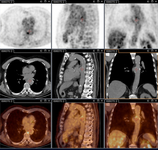

Aneurisma micótico na aorta torácica da febre Q diagnosticado na PET: PET/TC com 18-fluordesoxiglucose. Neste paciente assintomático com história de valva cardíaca e sorologia elevada, a PET permitiu diagnosticar endocardite aórtica na valva nativa com aneurismas micóticos da aorta torácica e lombar

Institut Hospitalo-Universitaire Méditerranée Infection (obtido consentimento do paciente)

Endocardite por febre Q diagnosticada na PET: PET/TC com 18-fluordesoxiglucose. Neste paciente assintomático com história de valva cardíaca e sorologia elevada, a PET permitiu diagnosticar endocardite aórtica na valva nativa com aneurismas micóticos da aorta torácica e lombar

Aneurisma micótico na aorta lombar da febre Q diagnosticado na PET: PET/TC com 18-fluordesoxiglucose. Neste paciente assintomático com história de valva cardíaca e sorologia elevada, a PET permitiu diagnosticar endocardite aórtica na valva nativa com aneurismas micóticos da aorta torácica e lombar